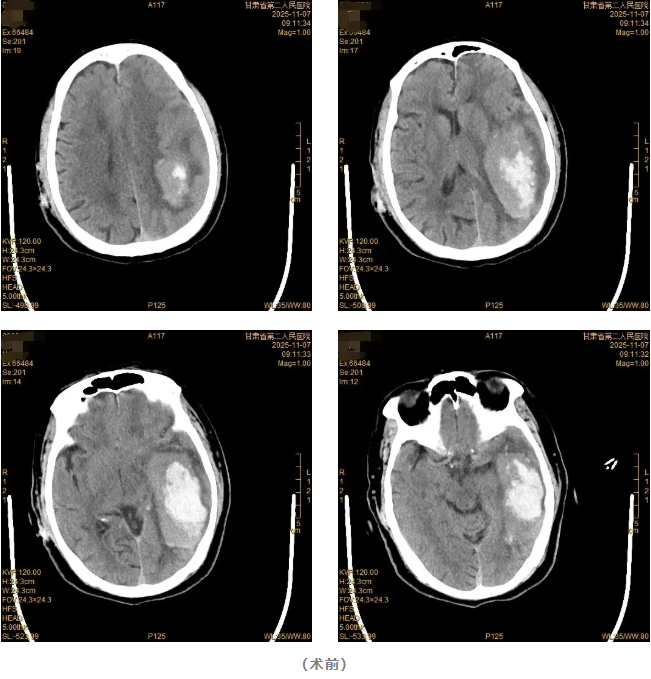

该患者因“突发意识不清伴右侧肢体无力9小时”由120急救车送至我院。急诊查头颅CT显示:左侧颞顶叶脑出血,出血量约70ml。神经疾病中心团队迅速完善术前准备后,急诊为患者施行开颅血肿清除手术。手术过程顺利,术后患者意识逐渐恢复清醒,复查头颅CT确认颅内血肿已清除。